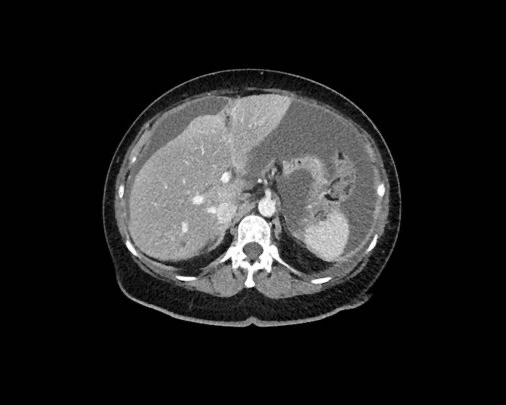

Ở vùng bụng trên, cơ hoành và dây chằng liềm cần được chú ý đặc biệt.

Các vị trí điển hình khác bao gồm rãnh cạnh đại tràng, túi cùng trực tràng-bàng quang hoặc trực tràng-tử cung, dây chằng liềm và mặt bụng của cơ hoành.

Cơ hoành

Do tác động của hô hấp, các tế bào khối u tự do bị hút vào mặt bụng của cơ hoành.

Các nốt cấy ghép này thường bị đánh giá thấp hoặc bỏ sót trên các lát cắt axial và được ghi nhận rõ hơn nhiều trên các mặt phẳng coronal hoặc sagittal.

Trong trường hợp này, các nốt khối u hiện diện rõ ràng và bao phủ phúc mạc gan.